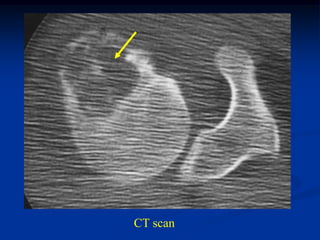

Case #610

14 year male with sessile based osteochondroma humerus

Bone scan

Coronal T-1 MRI

Cut surgical

specimen

cap

cartilage cap

Photomic